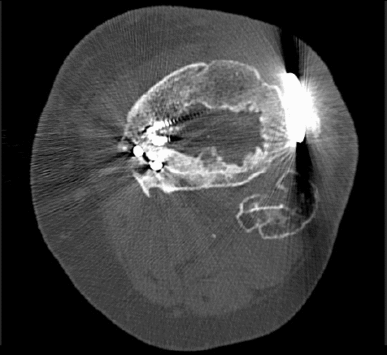

Entre sus áreas de especialización, se encuentran el tratamiento de fracturas complejas, la cirugía de pelvis y acetábulo mínimamente invasiva y la reconstrucción ósea con fijadores circulares para el tratamiento de pseudoartrosis e infecciones.

Puede ocurrir tras fracturas, cirugías o heridas cerca del hueso causada generalmente por bacterias.